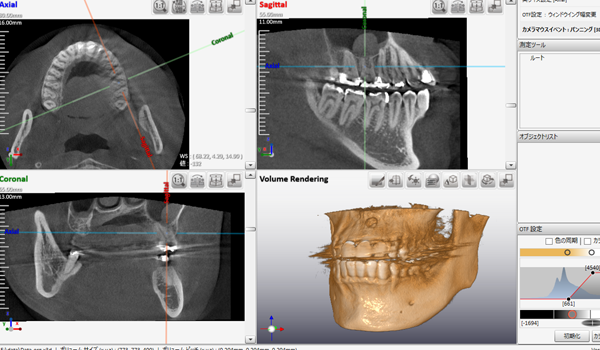

コンピュータを駆使しデータ処理と画像の再構成を行うことで、断層写真を得ることができる装置です。

歯科用CTとは、歯科に特化したCT装置で、コーンビームCTとも言われています。

歯科用CTとは、コーンビーム式のスキャンを行う事で、短時間のX線照射による、歪みの少ない繊細な画像を得ることができます。